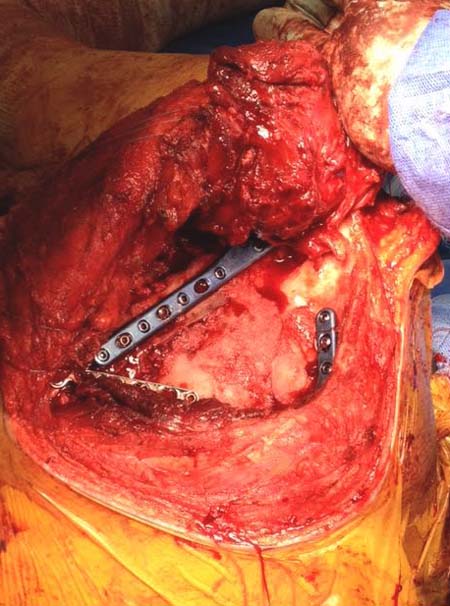

Здесь пример, стандартные снимки: плечо и лопатка прямой снимок,

аксиллярный и косой снимки (Y-view) и фиксация пластинами по краям, где

имеется более твердая кость. Специальные пластины, хотя любая 2.7 или

3.5 мм тубулярная пластина подойдут для фиксации перелома. Риск операции

- это повреждение нерва во время доступа и ре-фиксация ротаторной

манжетки если потребуется широкий доступ!